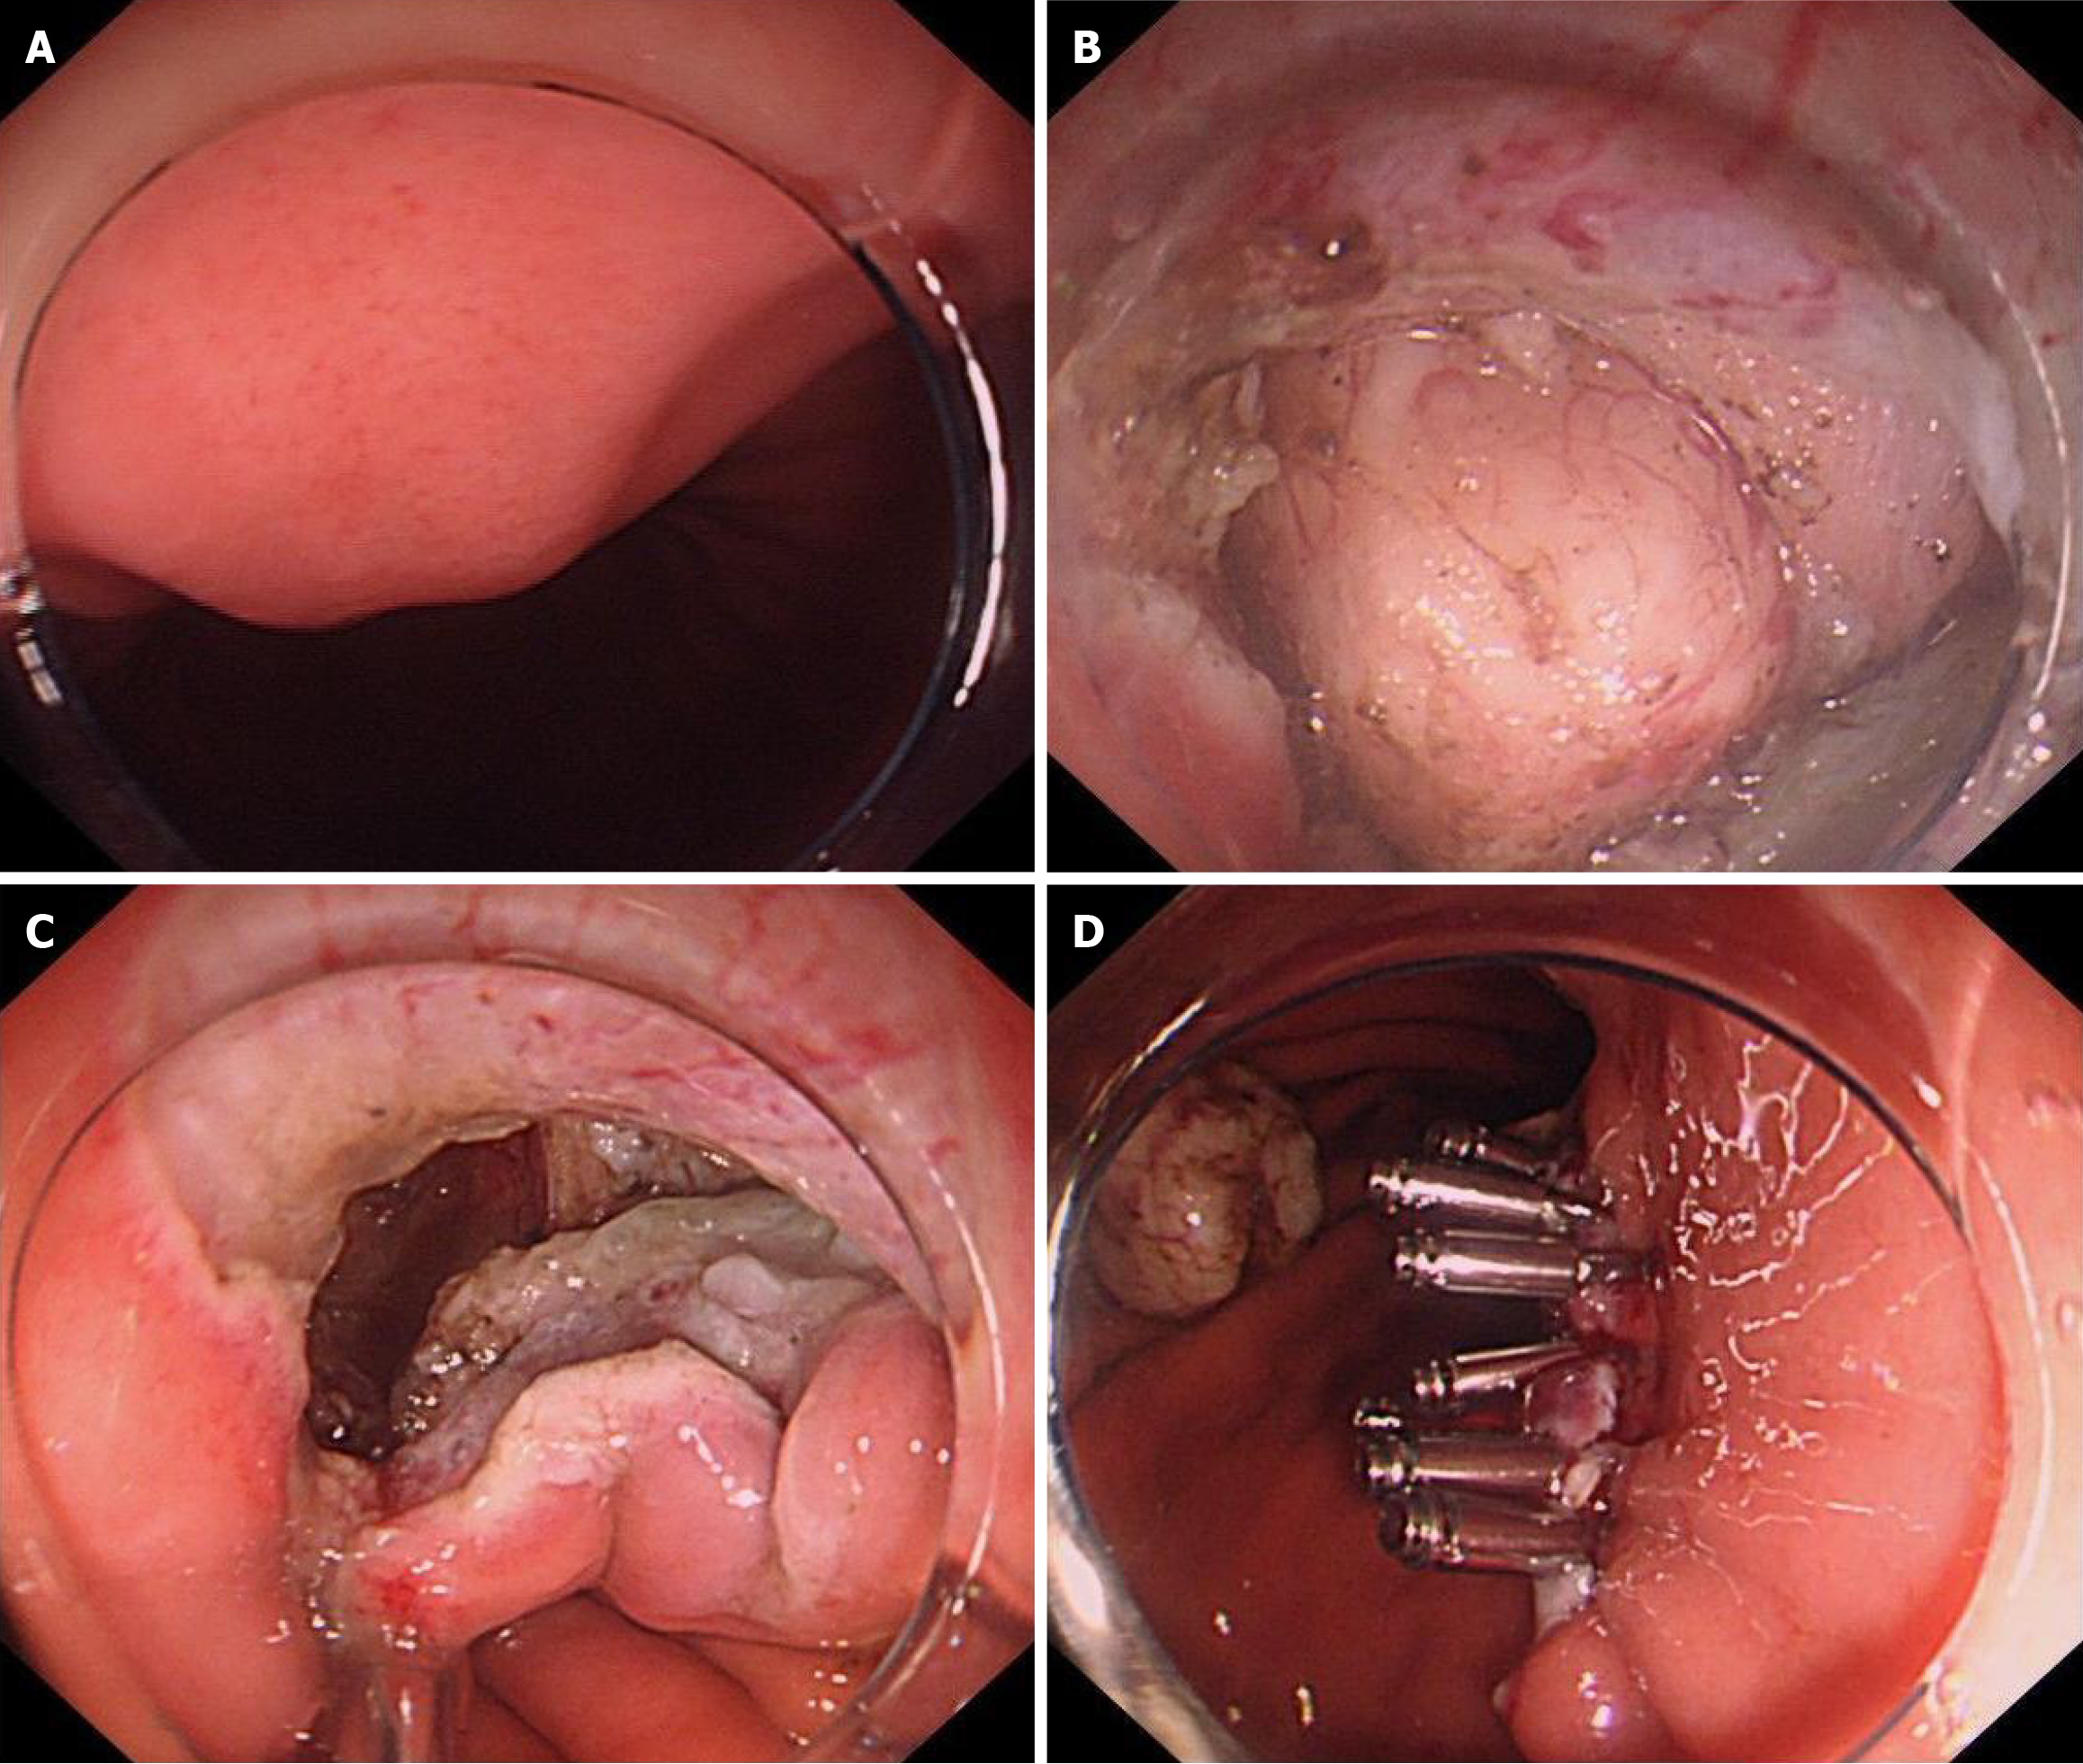

Control group (traditional closure group): Following the complete resection of the lesion, the wound was closed. Smaller wounds were closed with metal clips, larger wounds were managed using purse-string closures (Figure 2).